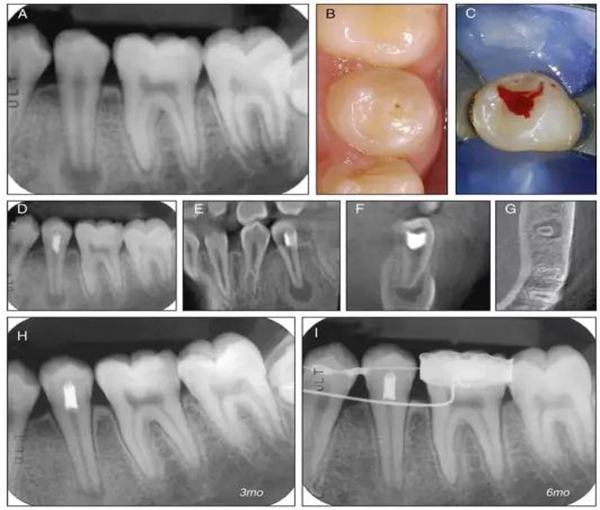

原則上年輕恒牙的牙髓治療應(yīng)盡可能以保存活髓的方式以便不影響牙根繼續(xù)發(fā)育。本文3個(gè)病例均描述了根尖尚未發(fā)育完成的下頜前磨牙被確診為牙髓壞死伴有大面積根尖病損,治療過(guò)程中在根管內(nèi)發(fā)現(xiàn)了部分活髓,而采用活髓切斷后都取得了很好的療效。